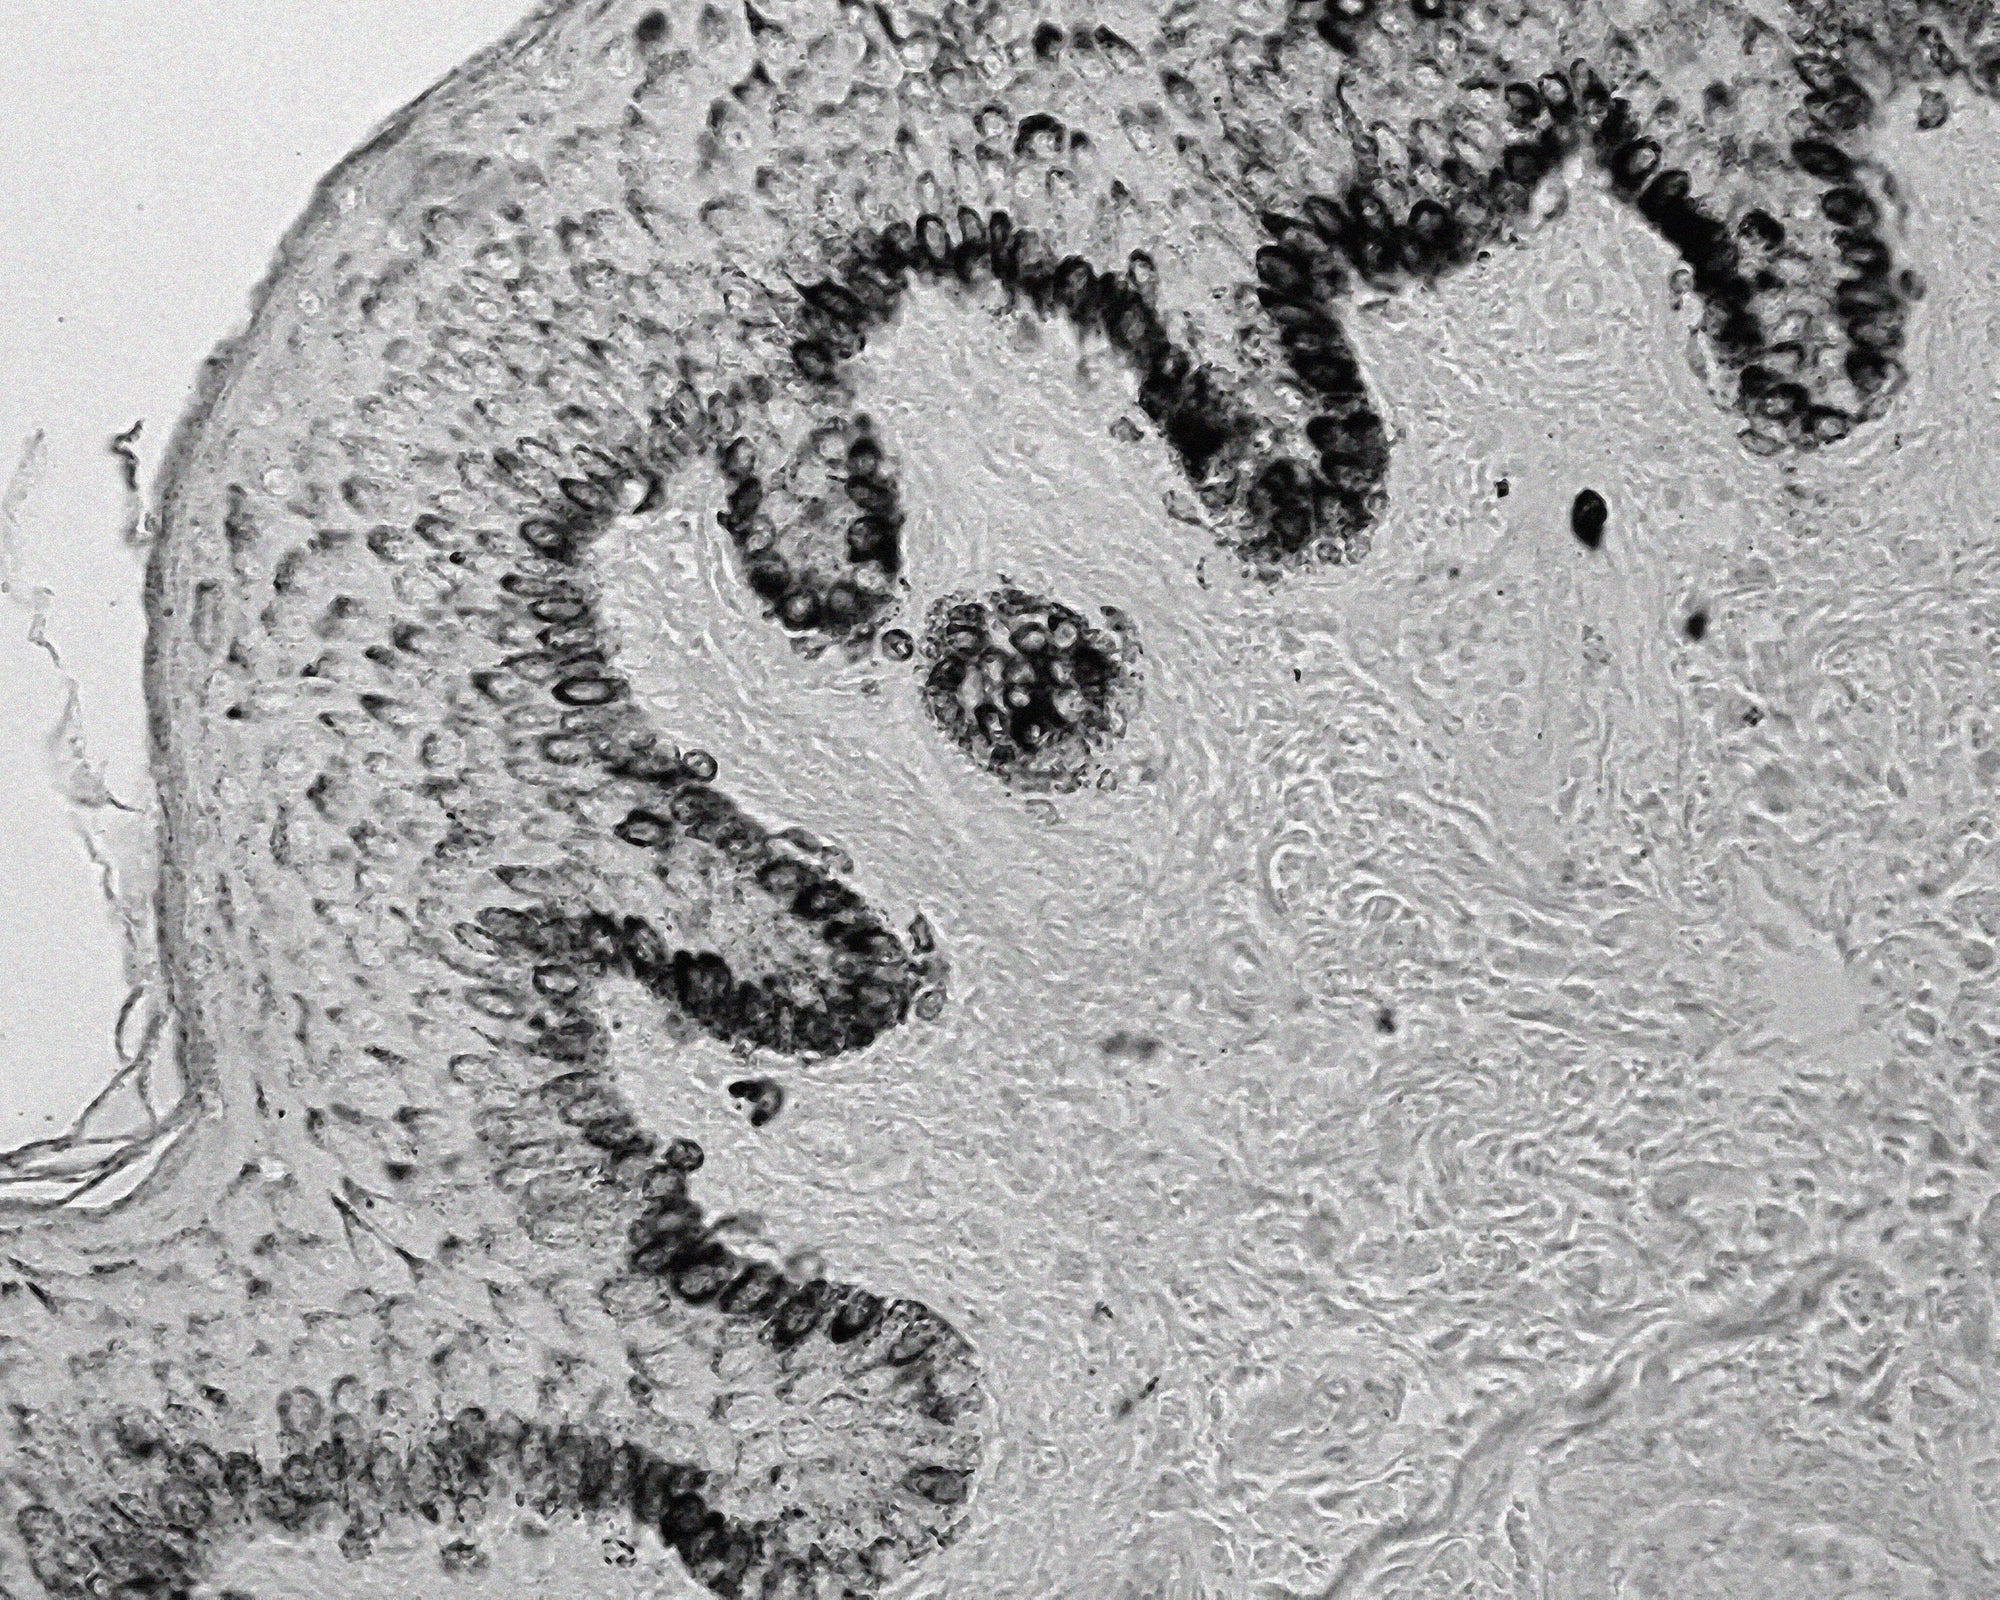

What is hyperpigmentation - the melanin process

Melanin starts its journey in melanocytes, specialised cells tucked into the basal layer (innermost layer) of the skin’s epidermis (outermost layer). These cells churn out melanin through a finely tuned process, packaging it into tiny sacs called melanosomes. From there, melanosomes transfer into neighbouring cells called keratinocytes. These cells travel upward through the skin’s layers and as they rise, melanin becomes visible, giving your skin its tone.

In healthy skin, this pigmentation process works in harmony to create an even complexion. However, external and internal factors—such as UV exposure, hormonal changes, and post-inflammatory responses—can disrupt this balance. The result is a buildup of melanin in certain areas, leading to hyperpigmentation, visible as dark spots, uneven skin tone, or discolouration on the face.